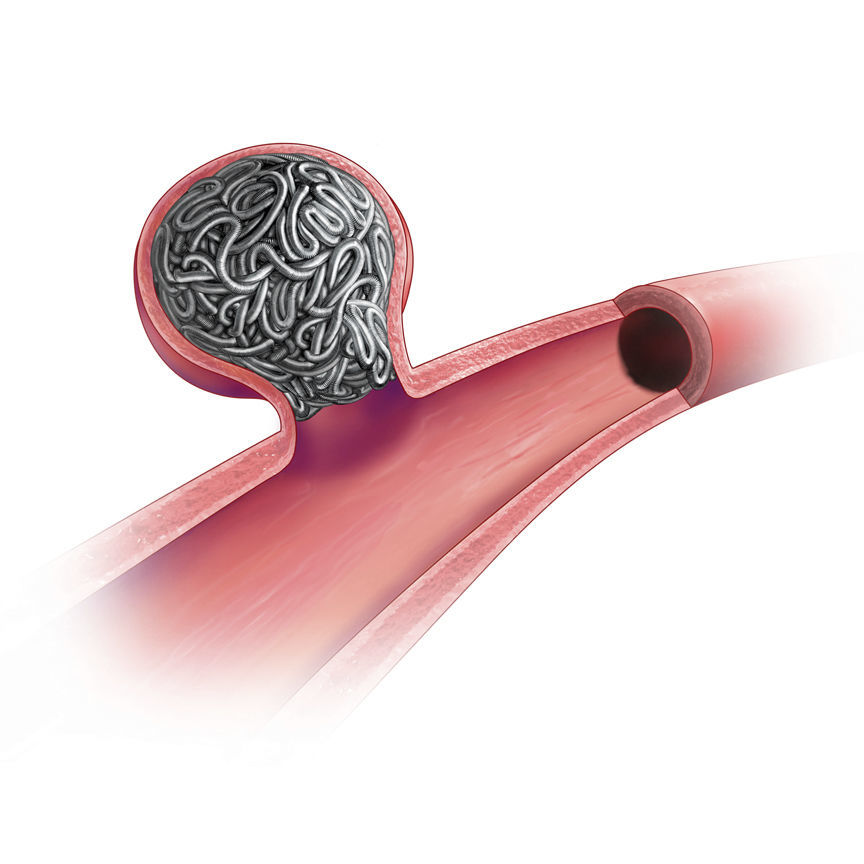

What Are Penumbra Coils Made Of . the penumbra embolization platform consists of ruby coil®, pod® (penumbra occlusion device), and packing coil, with newer iterations like ruby coil lp and packing coil lp offering extended lengths (up to 70 cm) and soft the penumbra lp coil system is indicated for the embolization of: penumbra’s embolization platform is made up of three unique detachable coil technologies: Ruby ® coil lp & packing coil lp offer the same technology as penumbra’s large volume system. ruby coil allows physicians to use longer and larger volume coils, potentially reducing procedural time and. penumbra’s embolization platform is composed of five detachable technologies:

penumbra’s embolization platform is composed of five detachable technologies: the penumbra lp coil system is indicated for the embolization of: ruby coil allows physicians to use longer and larger volume coils, potentially reducing procedural time and. the penumbra embolization platform consists of ruby coil®, pod® (penumbra occlusion device), and packing coil, with newer iterations like ruby coil lp and packing coil lp offering extended lengths (up to 70 cm) and soft Ruby ® coil lp & packing coil lp offer the same technology as penumbra’s large volume system. penumbra’s embolization platform is made up of three unique detachable coil technologies:

What Are Penumbra Coils Made Of the penumbra embolization platform consists of ruby coil®, pod® (penumbra occlusion device), and packing coil, with newer iterations like ruby coil lp and packing coil lp offering extended lengths (up to 70 cm) and soft the penumbra lp coil system is indicated for the embolization of: ruby coil allows physicians to use longer and larger volume coils, potentially reducing procedural time and. Ruby ® coil lp & packing coil lp offer the same technology as penumbra’s large volume system. penumbra’s embolization platform is made up of three unique detachable coil technologies: the penumbra embolization platform consists of ruby coil®, pod® (penumbra occlusion device), and packing coil, with newer iterations like ruby coil lp and packing coil lp offering extended lengths (up to 70 cm) and soft penumbra’s embolization platform is composed of five detachable technologies: